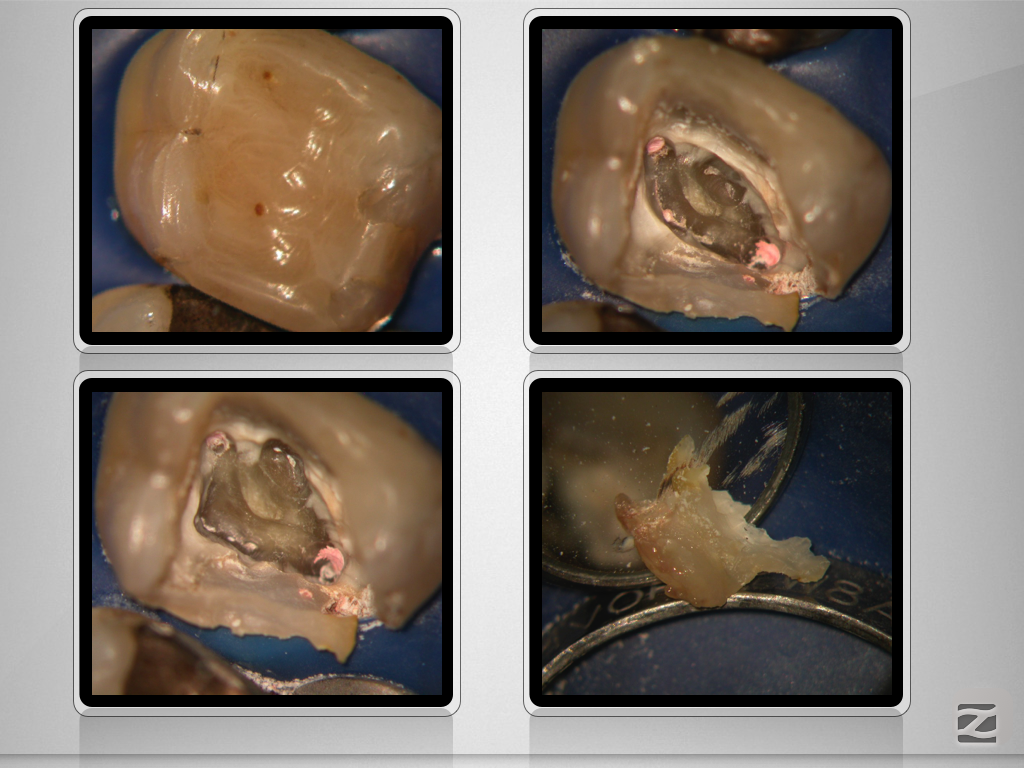

Deutliche Krümmung und kein DVT!